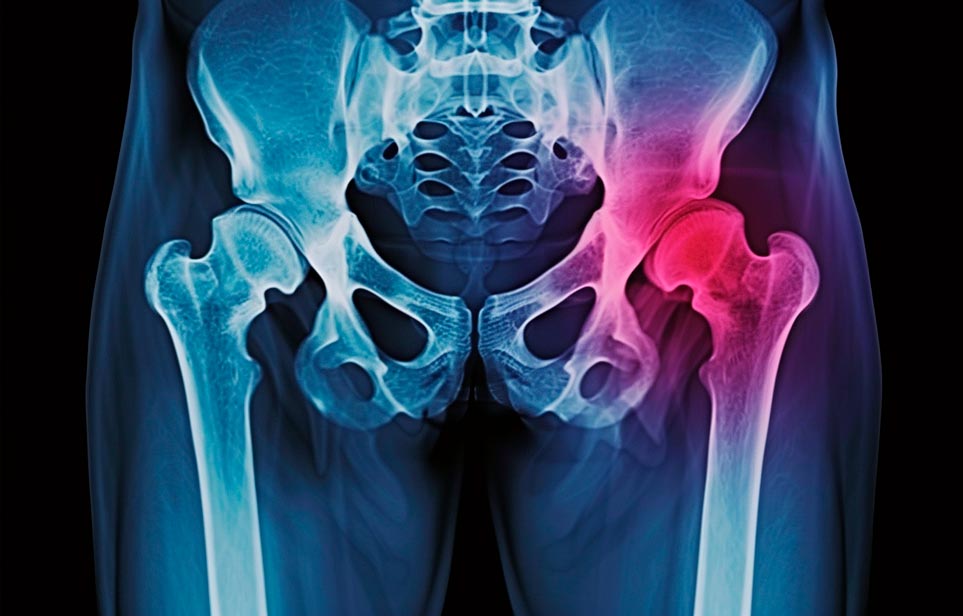

Реабилитация пожилых после перелома шейки бедра в Ефремове

Такая травма в большей части случаев возникает у граждан преклонного возраста. При её появлении на протяжении длительного времени сохраняются болевые и неприятные ощущения в области паха, при которых серьёзно ухудшается качество жизни, возникает множество последствий для его жизни и здоровья.

По какой симптоматике можно определить перелом шейки бедра?

Выявить его можно по возникновению следующей тревожной симптоматики:

- Визуально повреждённая нога сокращается на несколько сантиметром из-за сокращения мышц.

- Стопа выворачивается наружу.

- В лежачем положении человек не может поднять ногу.

При такой симптоматике важно незамедлительно обращаться к специалистам для получения всей необходимой помощи, терапии и восстановления после перелома шейки бедра. Если не оказать помощи старику, то это приведёт к гноению, инвалидности, иным видам осложнений.